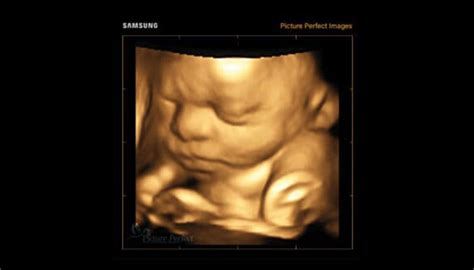

- Ecografia: Rolul ecografiei în determinarea sexului bebelușului este crucial în procesul de planificare a viitorului familiei. În general, ecografia pentru determinarea sexului bebelușului este efectuată în jurul săptămânii 16-20 de sarcină, când organele genitale ale fătului sunt suficient de dezvoltate pentru a fi vizibile. Precizia ecografiei în determinarea sexului bebelușului depinde de poziția fătului și de experiența ecografistului. În general, precizia este de peste 90%, dar aceasta poate varia.